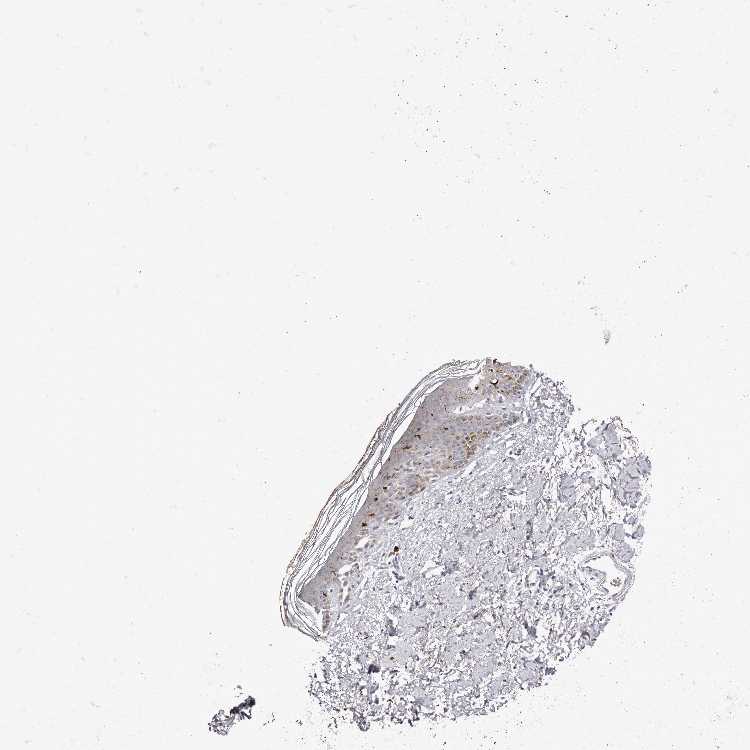

SKIN 1 - Antibody stainingi

Antibody staining in the annotated cell types in the current human tissue is reported as not detected, low, medium, or high, based on conventional immunohistochemistry profiling in selected tissues. This score is based on the combination of the staining intensity and fraction of stained cells.

Each image is clickable and will lead to virtual microscopy that enables deeper exploration of all samples and also displays staining intensity scores, fraction scores and subcellular localization as well as patient and tissue information for each sample.

Antibody HPA029683

Langerhans High

Fibroblasts Not detected

Keratinocytes Low

Melanocytes Low